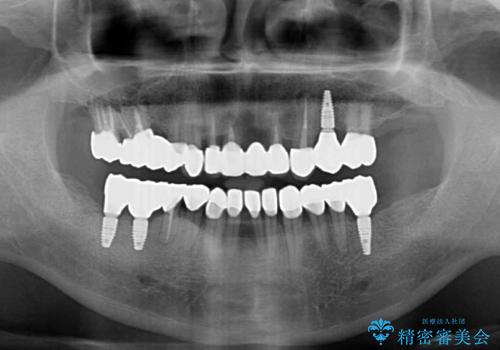

欠損と虫歯だらけの口の中 真っ白なセラミック治療

- 奥歯の欠損や、ボロボロになった歯を気にして来院された患者様です。

転勤で東京にいる1年間の間に治療を終えたいとのことで、奥歯のインプラント埋入や前歯部の歯周外科処置など、治癒に時間を要するものから始めていき、治癒期間に根管治療や補綴治療を進めて行くこととしました。

インプラントにより奥歯の咬み合わせが安定し、上顎前歯の歯肉ラインを調整するための骨外科処置により深く咬みこんでいた前歯部も負担のかからない咬み合わせに改善することができました。